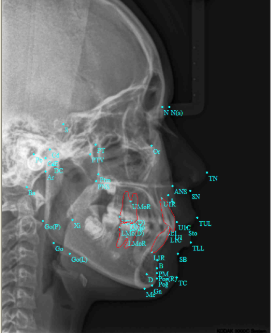

牙弓对脸型的影响↓

大众的审美都认为中型面孔为最好看的面孔,两侧对称,协调自然,并各自与个体的面型、牙型相一致,这是专业正畸医生需要全面评估的。这不仅能保持牙在颌骨上的稳固性,以便发挥其最大的咀嚼功能,并能保护牙周组织的健康及支持颌面部的软组织,使颜面外形丰满美观。

正畸不单纯只是把窄的扩宽,宽的变窄这么简单,还需要根据你的面型设计出最适合你的方案。

③在脸型发育方面,上颌骨的狭窄通常容易导致下颌骨后缩,影响下颌骨的进一步发育,可能会导龅牙等问题。

②18岁以后,也就是生长发育停止后,这个时候如果要治疗的话,单纯的牙齿矫正不能把畸形的颌骨复位,所以一般医生会建议正畸正颌联合治疗。成年人正畸治疗后效果↓